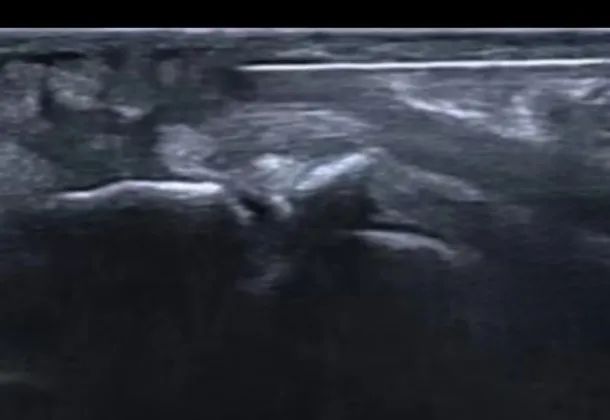

超声可视化针刀微创技术能够在超声引导实时反映病变部位的组织结构、形态、性质等情况,帮助临床医生更加准确的进行术前诊断。实时监控针刀在组织内的位置,以及与周围神经血管的毗邻关系,避免不必要的刺激或切割,提高治疗的精准性和安全性。超声可视下精准治疗,可减轻患者恐惧感,提升患者就医体验。